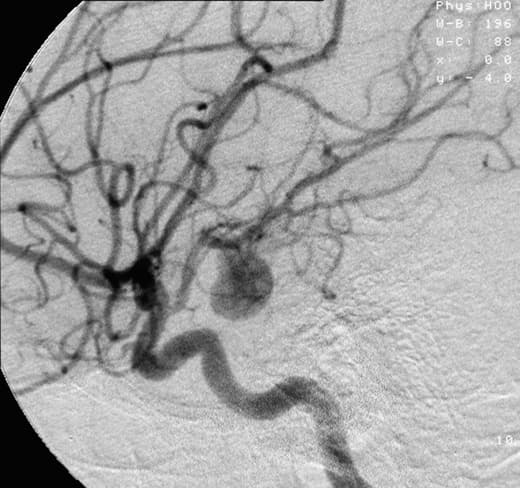

An aneurysm is an outward bulging, likened to a bubble or balloon, caused by a localized, abnormal, weak spot on a blood vessel wall. Aneurysms may be a result of a hereditary condition or an acquired disease. Aneurysms can also be a nidus (starting point) for clot formation (thrombosis) and embolization. As an aneurysm increases in size, the risk of rupture, which leads to uncontrolled bleeding, increases. Although they may occur in any blood vessel, particularly lethal examples include aneurysms of the Circle of Willis in the brain, aortic aneurysms affecting the thoracic aorta, and abdominal aortic aneurysms. Aneurysms can arise in the heart itself following a heart attack, including both ventricular and atrial septal aneurysms. There are congenital atrial septal aneurysms, a rare heart defect. The word is from Greek: ἀνεύρυσμα, aneurysma, "dilation", from ἀνευρύνειν, aneurynein, "to dilate". Aneurysms are classified by type, morphology, or location. A true aneurysm is one that involves all three layers of the wall of an artery (intima, media and adventitia). True aneurysms include atherosclerotic, syphilitic, and congenital aneurysms, as well as ventricular aneurysms that follow transmural myocardial infarctions (aneurysms that involve all layers of the attenuated wall of the heart are also considered true aneurysms). A false aneurysm, or pseudoaneurysm, is a collection of blood leaking completely out of an artery or vein but confined next to the vessel by the surrounding tissue. This blood-filled cavity will eventually either thrombose (clot) enough to seal the leak or rupture out of the surrounding tissue. Pseudoaneurysms can be caused by trauma that punctures the artery, such as knife and bullet wounds, as a result of percutaneous surgical procedures such as coronary angiography or arterial grafting, or use of an artery for injection. Aneurysms can also be classified by their macroscopic shapes and sizes and are described as either saccular or fusiform. The shape of an aneurysm is not specific for a specific disease.